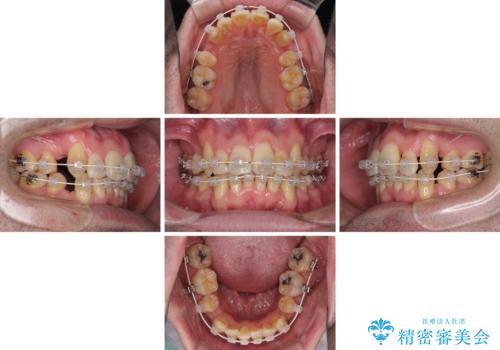

ものが挟まる 著しい叢生を解消 ワイヤー装置による抜歯矯正

- 前歯のデコボコを気にして来院された患者様です。

叢生の解消とともに、前方に張り出した上顎前歯を引っ込めることを目的とし、上下左右の第一小臼歯4歯を抜歯をしてワイヤー矯正により治療することとしました。

治療開始直後は、あっという間に歯列が整い、すぐに終わるのではないかと思われましたが、治療の後半にブラックトライアングル解消のための処置を行ったため、当初予定していた2年半ほどの期間を要することとなりました。